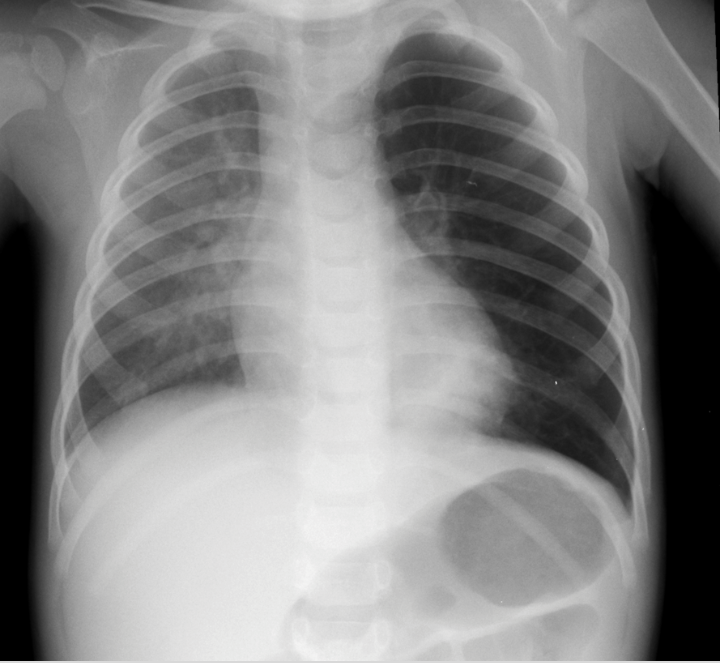

Pediatric Chest X-ray

Pneumothorax

Left sided pnumothorax